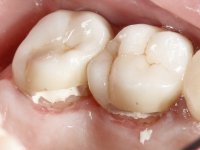

Male patient, 34 years old, non-smoker. Teeth 17 and 16 had extensive restorations with composite resin and placed intra-radicular posts. In the imaging examination, it was found that the endodontic treatment was not technically satisfactory, but had been asymptomatic for several years. The patient was rehabilitated with a 2-element bridge at 17 and 16 and 4 years later an abscess appeared in the apical area of 2.6. It had the 2.8 tooth included with a close relationship with the 2.7 root. During these 4 years there was no positional change of this tooth. After endodontic retreatment of teeth 27 and 26, an abscess appears again in the area of tooth 26, possibly associated with a root fracture. Given the history referred to in relation to tooth 26, it was considered a tooth with indicated extraction.

Teeth 17 and 16 were prepared for the fabrication of a 2-element Zr bridge. The impression was performed with a double mixing technique and a monolithic bridge in Zr was made in the laboratory. 4 years later, an abscess appeared in the apical area of tooth 26. It was decided to remove the bridge, remove the intra-radicular posts and retract the endodontic treatments of teeth 17 and 16. The removal of the bridge was carried out by making two cervical cavities. in the palatal area of the bridge and with a microluxator, disinsertion movements were performed. The intra-radicular posts were removed using fine drills and an ultrasound tip. The bridge was provisionally cemented and the patient was referred to a fellow endodontist for endodontic retreatment. After the retreatment, the intraradicular posts were placed again and the bridge was definitively cemented. One year later, a new abscess appears, possibly related to a root fracture. The bridge was sectioned between tooth 27 and 26 and tooth 26 was extracted and the crown of 27 was provisionally cemented. 3 months later, teeth 27 and 25 were prepared and a temporary bridge was made in dual polymerization resin. Then, an impression was made using the double mixing technique and a 3-element bridge in Zr was made in the laboratory. It was permanently cemented in the mouth with resin-reinforced glass ionomer cement.